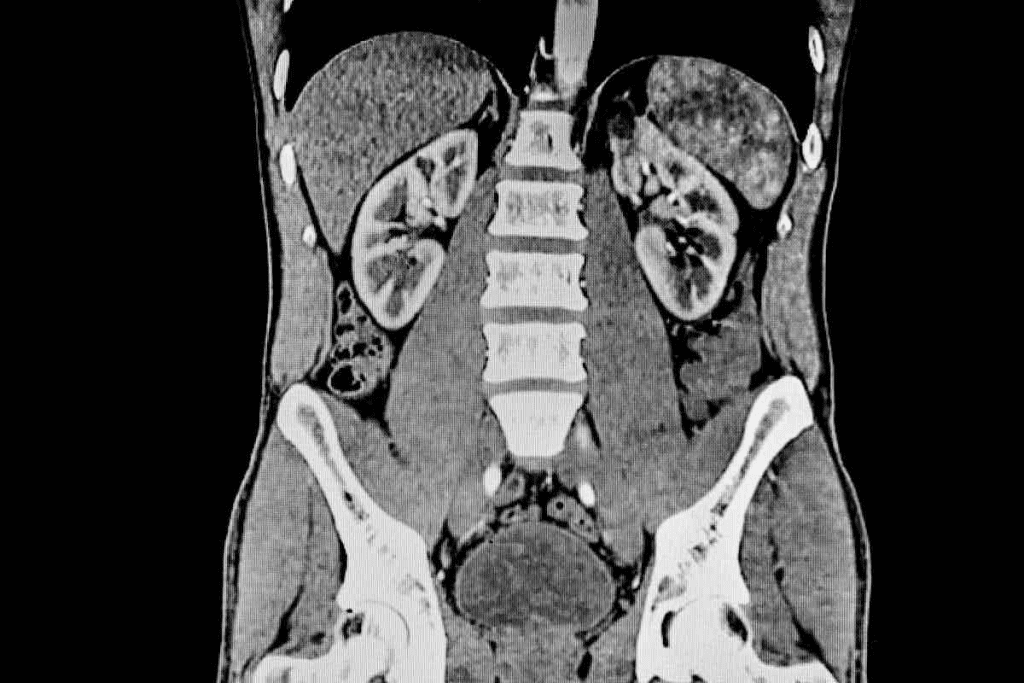

Image 4: Normal CT of Abdomen: Renal Structures

Understanding the normal CT scan images of the abdomen is key for radiologists. They look closely at the kidneys. They check the kidneys’ shape, how they light up after contrast, and if the collecting system and ureters are okay.

Kidney Morphology and Enhancement

The kidneys should look normal on a CT scan. They should have a smooth shape and be the same size. After contrast, you can see the different parts of the kidney.

Key features of normal kidney morphology on CT include:

- Smooth renal contour

- Symmetric size

- Normal cortical thickness

- Typical enhancement patterns after contrast administration

Collecting System and Ureters

The collecting system, like the renal calyces and pelvis, is checked for any issues. CT urography helps a lot with this. It looks at the kidneys, ureters, and bladder. The ureters are checked for any blockages or problems.

Normal characteristics of the collecting system and ureters on CT:

- Non-dilated renal calyces and pelvis

- Normal ureteral caliber and course

- Absence of filling defects or obstructing lesions

Knowing what a normal kidney looks like on a CT scan helps doctors find and treat kidney problems.

What is the normal CT appearance of the kidneys?

The kidneys look normal on CT scans if they’re the right shape and enhance properly after contrast. The collecting system and ureters are also checked for issues.